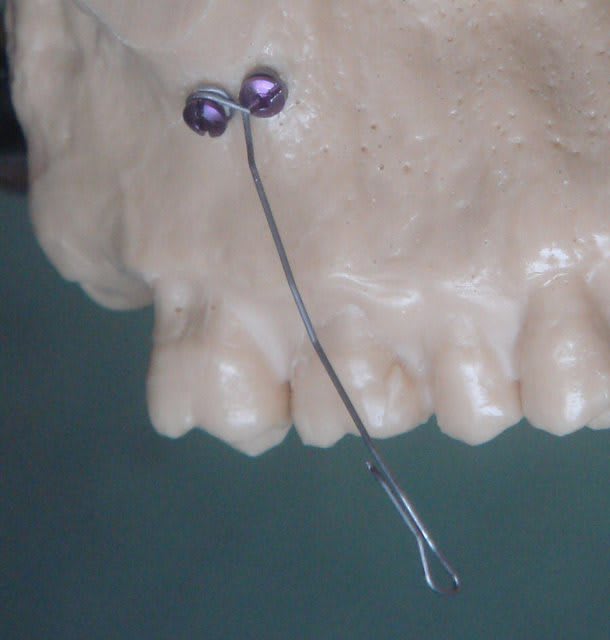

Le fil utilisé comme ressort pour tracter la caine s'appelle "CT8-1" = Cortical, TMA, terminaison en forme de "8", 1 bras.

S'il n'y avait qu'une seule boucle et une seule vis, on ne pourrait avoir qu'un contrôle "2D", avec deux vis on obtient un contrôle "3D".

Après une incision d'environ 10 mm en fond de vestibule et rugination du périoste, une vis avec sa connectique est placée très simplement à l'aide du tournevis adéquat..

La seconde vis est enfilée dans la boucle restante et la plaie est laissée sans points de suture, la pression musculaire étant suffisante pour la coaptation des berges de la plaie. Quasiment pas de suite opératoire, uniquement un antalgique type paracétamol..